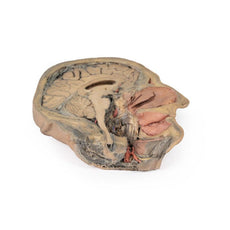

3D Printed Sagittal Section of Head with Infratemporal Fossa Dissection

This 3D model provides a combined midsagittal section through the head and

superior neck coupled with a deep dissection into the infratemporal fossa

region and superficial dissection of the scalp.

In the preserved midsagittal section there is preservation of the endocranial

contents, the nasal and oral cavities, and the pharynx to the level of the

laryngeal cartilages. The nasal cavity is preserved nearly intact, except for a

small window excised into the middle nasal concha to expose the ethmoid

air cells. A very large sphenoid sinus exists in the individual just superior

to the torus of the auditory tube in the nasopharynx. The oral cavity and

laryngopharynx are undissected, with the larynx only preserve just distal to the

level of the arytenoid cartilages and not including a clear set of vocal folds.

Within the endocranial cavity, the sectioned brain is slightly off the midagittal

plane, such that neither the superior sagittal sinus nor the third ventricle are

clearly defined - but the lateral ventricle is open and part of the fourth ventricle

is preserved between the pons and cerebellum. The gyri and sulci of the

cerebrum are not well separated, but the cingulate gyrus and corpus callosum

can be separated. Cross-sectioned views of the optic tract, pituitary gland,

superior and inferior colliculi, superior cerebellar peduncle, and transition

between the medulla oblongata and spinal cord are all visible. The tentorium

cerebelli and confluence/transverse sinus is positioned between the

cerebellar hemisphere and occipital lobe. Small portions of the posterior

inferior cerebellar artery, vertebral arteries, basilar artery, and posterior

cerebral and anterior cerebral arteries are visible in section.